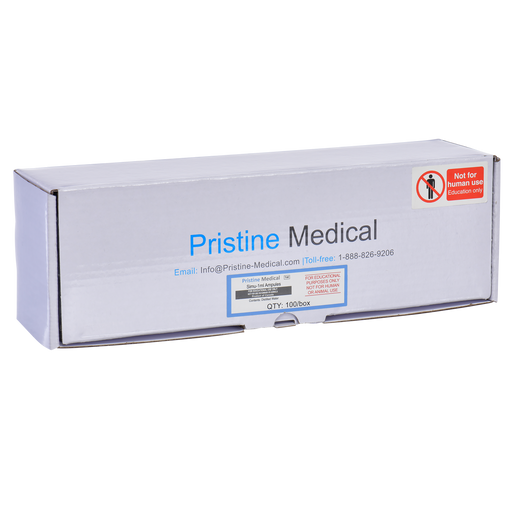

The Anatomy Lab Femoral Arteriovenous Puncture and Abdominocentesis Ultrasound Training Model is designed for durability and consistent performance. Whether used for simulation practice or demonstration, you can rely on the long-lasting quality and reliability of this ultrasound training model.